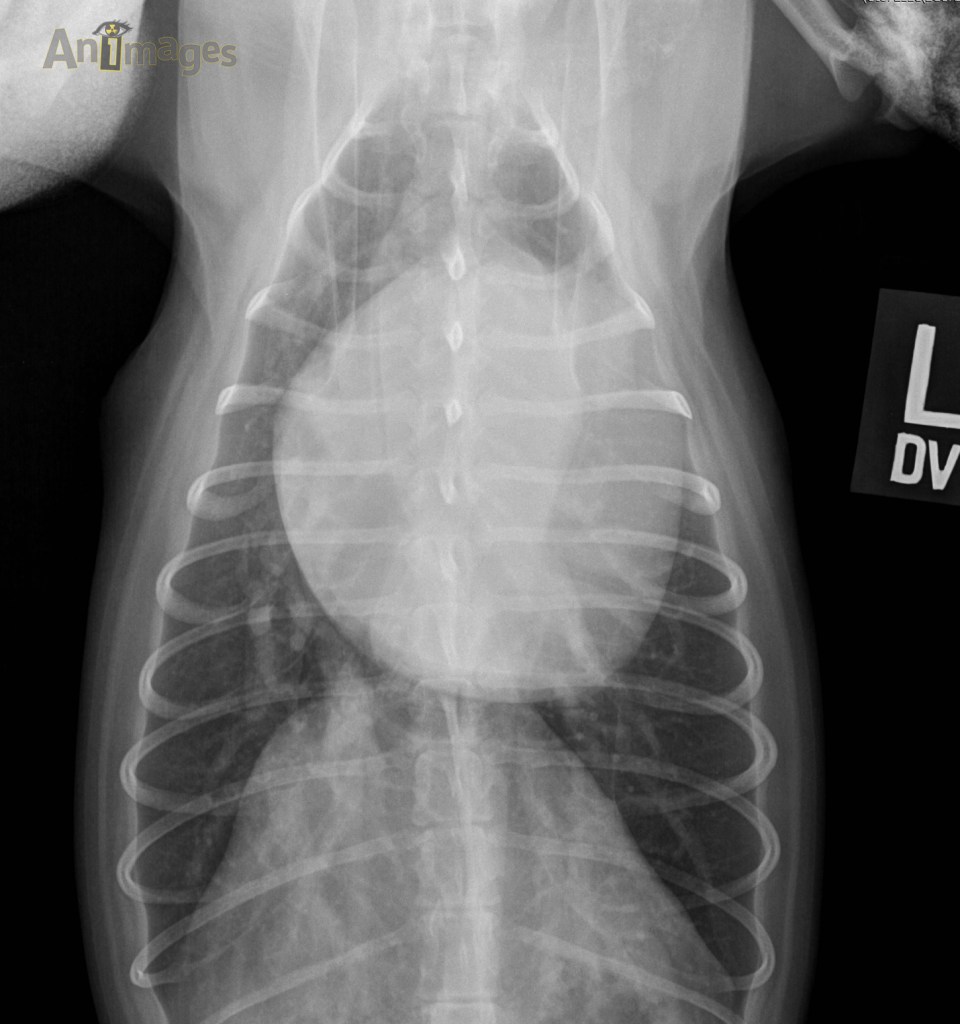

Dorsoventrale